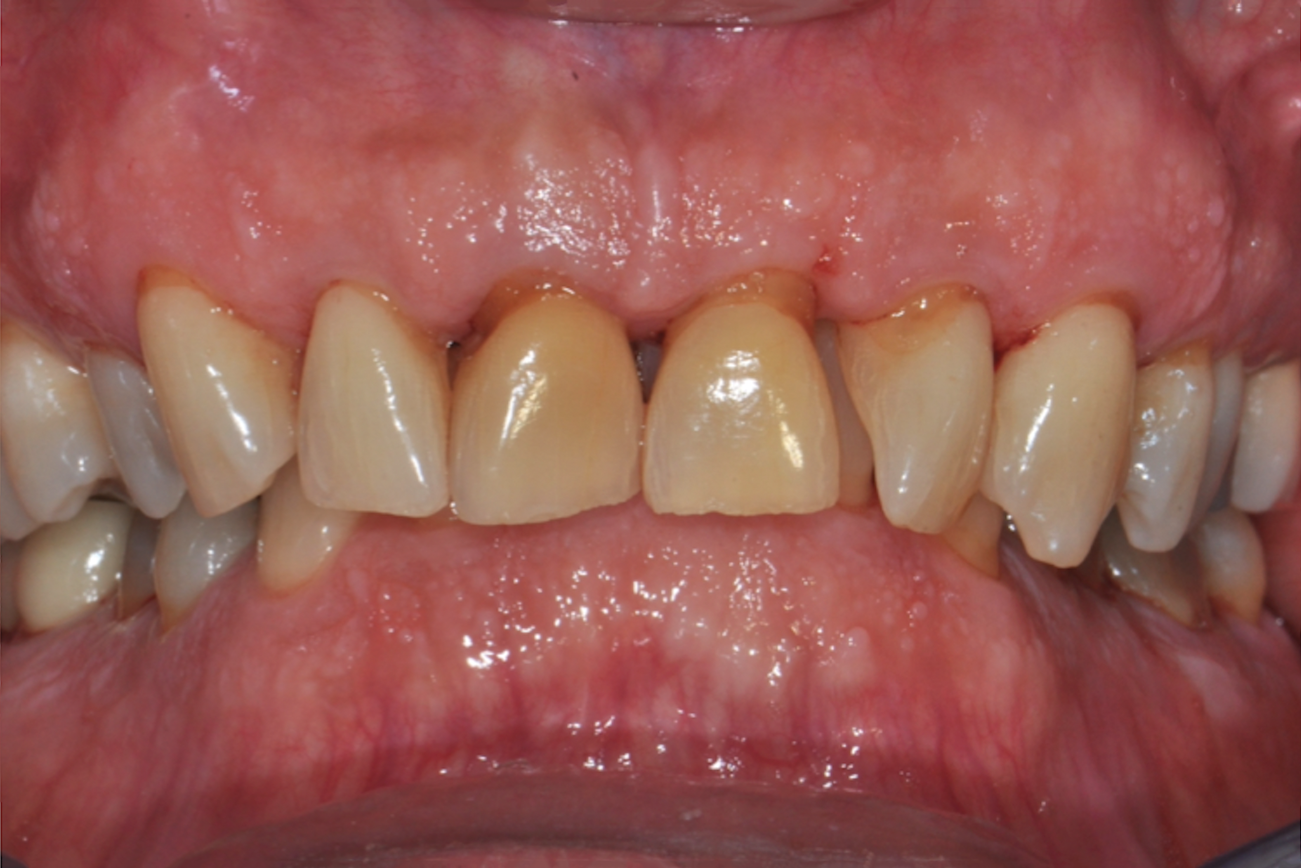

Fig 10. Clinical views at 4-year follow-up: right lateral (Fig 10), frontal (Fig 11), and left lateral (Fig 12). There was significant reduction in PD, BOP, and mobility.

Figure 10

In 2018, however, the patient noticed significantly increased bleeding and tenderness associated with his non-scored mandibular left molars (Nos. 17 and 18), which he then elected to retreat with laser-assisted periodontal therapy. This retreatment was successful in eliminating his symptoms and resulted in periodontal stability (Figure 10 through Figure 13).

The patient was motivated by the continued discussions of his PRS and 15-year prognosis, and determined to maintain excellent compliance to the "keys to success." His maintenance plan included the use of a water flosser, flossing, and diluted oral sodium hypochlorite (NaOCl) bleach mouthrinse (dilution ratio of a half teaspoon of NaOCl to 8 ounces of warm water), which was used in his water irrigator device. After 4 years of therapy and maintenance, his PRS score was reduced from 8 to 5, thus lowering his periodontal risk and demonstrating the effectiveness of the PRS strategy.